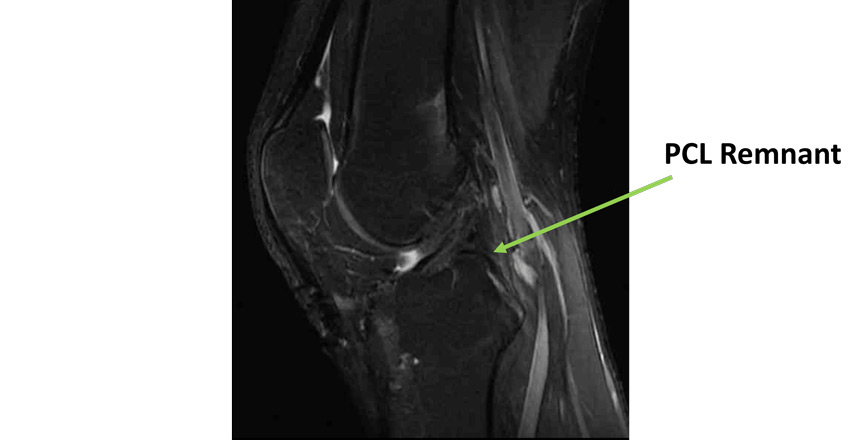

Pre operative MRI

- Knee MRI Findings:

- Rupture of the PCL, PLC and LCL

- Intact ACL

- No meniscal tear

- No cartilage injury